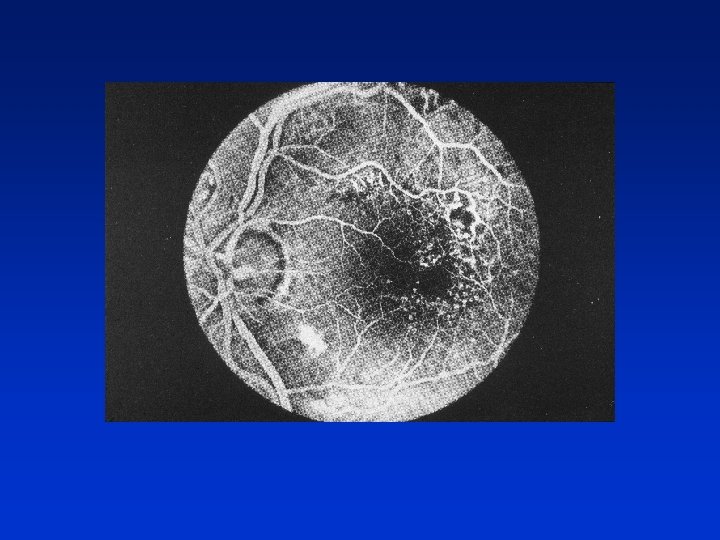

Proliferative Diabetic Retinopathy • New vessels elsewhere (NVE) • New disc vessels (NVD) High risk proliferative diabetic retinopathy - New vessels ( NVE/NVD) - Preretinal haemorrhage

Proliferative retinopathy causes total blindness in 70% of untreated eyes after 5 years onset of neovascularisation

Treatment of NVE Mild NVE – focal treatment Severe NVE – PRP (600 – 800 burns)

Treatment of NVD PRP 1500 – 3000 burns